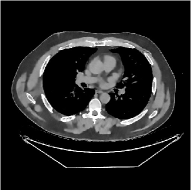

This section compares the reconstruction quality and runtime among the proposed MBIR method, PWLS-ST-, and other three MBIR methods, PWLS-EP, PWLS-DL, and PWLS-ST-. Table I shows that, for both 2D and 3D sparse-view CT reconstructions of the XCAT phantom, the proposed PWLS-ST- model outperforms PWLS-EP and PWLS-ST- in terms of RMSE. In addition, PWLS-ST- using a square transform (of size ) achieves lower RMSE than PWLS-DL using an overcomplete dictionary (of size ) for 2D sparse-view reconstructions. Fig. 3(a) and Fig. 4 show the reconstructed images for 2D and 3D phantom experiments, with different reconstruction models and different number of views. (See the corresponding error maps in the supplement.) The proposed PWLS-ST- consistently gives more accurate image reconstructions compared to other MBIR methods. Specifically, PWLS-ST- has smaller errors in the heart region (see zoom-ins in Fig. 3(a)) of 2D reconstructions than PWLS-DL and PWLS-ST-. In addition, compared to PWLS-ST-, PWLS-DL and PWLS-ST- have some ringing artifacts around the edges with high transition, e.g., edges between air and soft tissues. (See a comparison of profiles of PWLS-ST- and PWLS-ST- in the supplement.) In particular, PWLS-ST- and PWLS-DL give more visible ringing artifacts for 2D reconstruction from fewer views, and PWLS-ST- has these ringing artifacts for 3D reconstructions regardless of the number of views (see zoom-ins in Fig. 4). Table II reports runtimes of different MBIR methods in reconstructing the -views XCAT phantom scan. (FBPConvNet is a non-MBIR method and its runtime for processing a image is approximately one second with a TITAN Xp GPU.) While providing better reconstruction quality, the proposed Algorithm 1 of PWLS-ST- has shorter runtime compared to the algorithms of PWLS-DL and PWLS-ST- in Section III-A. Similar to the PWLS-EP algorithm, the reconstruction time of the PWLS-DL, PWLS-ST-, and PWLS-ST- algorithms can be further reduced by using ordered subsets [51].

Fig. 3(b) shows that when tested on the clinical scan data, the proposed PWLS-ST- method improves reconstruction quality in terms of noise and artifacts removal (e.g., see zoom-ins for soft-issue regions), and edge preservation (e.g., see zoom-ins for bone regions), compared to PWLS-EP and PWLS-ST-. Compared to PWLS-DL, PWLS-ST- achieves comparable image quality, but requires less computational complexity.

The benefit of the proposed PWLS-ST- over PWLS-ST- can be explained when there exist some outliers for some : in (12) gives equal emphasis to all sparse codes – from small to large coefficients that generally correspond to edges in low- and high-contrast regions, respectively – in estimating ; however, PWLS-ST- adjusts to mainly minimize the outliers, i.e., it may not pay enough attention to reconstruct regions with small coefficients. The histogram results in Fig. 1 reveal model mismatch of PWLS-ST- over the iterations. Fig. 3, Fig. 4, and Table I show that PWLS-ST- can moderate model mismatch, and provides more accurate reconstruction than PWLS-ST-.

![]() |

| (a) 2D fan-beam CT experiments |